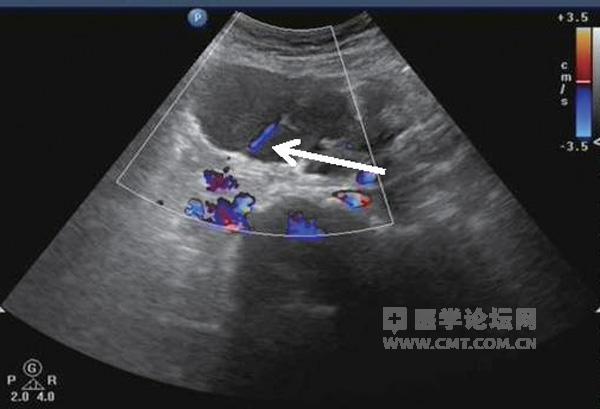

图4 子宫左上方囊肿分隔可见条状血流信号

超声检查 检查显示:子宫前位,体积增大7.3 cm×5.2 cm×6.3 cm,边界清,外形尚规则,子宫内膜前移。子宫肌层回声欠均匀,子宫后壁肌间隐约可见3.8 cm×3.5 cm×3.7 cm中等回声包块,边界欠清,点状血流信号(图1)。右附件可见6.7 cm×5.8 cm×5.3 cm囊性包块,边界清,外形规则,内为液性暗区伴细密光点,囊壁可见点状血流信号(图2和图3);子宫左上方可见6.1 cm×4.5 cm×4.6 cm囊性包块,边界清,外形尚规则,内为液性暗区伴细密光点,内可见分隔,隔壁可见条状血流信号(图4)。子宫直肠窝及髂窝无阳性发现。

卵巢子宫内膜异位囊肿又称为巧克力囊肿,二维声像图呈圆形或椭圆形,可以是双侧或单侧病变,囊肿内回声根据月经周期和病程长短不同而有一定特征性改变。彩色多普勒超声显示,少许血流信号,囊壁有中等阻力,低速血流频谱。上述患者囊肿内含细密光点及细分隔,须与输卵管和卵巢积脓鉴别。